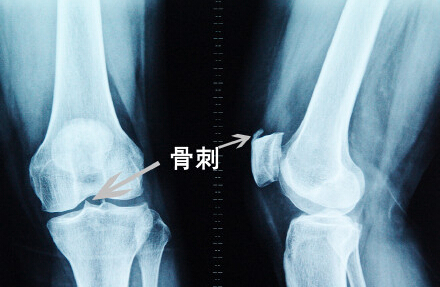

膝关节有骨刺是什么症状 (膝关节骨刺怎么缓解症状)

对于骨刺这种疾病人们一定不会感到陌生,生活中有很多人都有受到它的侵害,它常侵袭人体的负重关节炎,因此,膝关节不得幸免患病。膝关节骨质增生是一种慢性病变,随着病程的加长,关节活动功能也会逐步受限,膝关节活动可听到明显弹响声。那么,膝关节骨刺的常见症状有哪些?

膝关节骨刺的表现症状,膝关节骨刺的症状 膝关节骨刺的常见症状有哪些